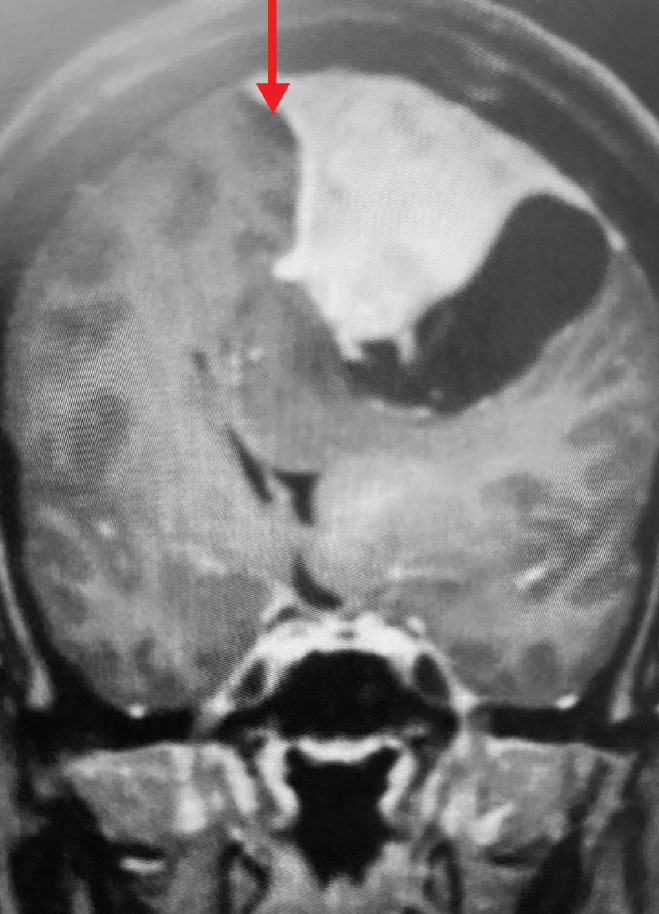

A) Pre-operative, post-contrast, coronal MRI. Arrow points to tumor involvement in the superior sagittal sinus

Fig 1. A) Pre-operative, post-contrast, coronal MRI. Arrow points to tumor involvement in the superior sagittal sinus.

This is a 55 year old right-handed woman who was having progressive balance problems. MRI with and without contrast demonstrated a 7 cm partly cystic meningioma involving the left frontal convexity and falx, and encasing the superior sagittal sinus. There was also tumor involvement of part of the convexity skull.